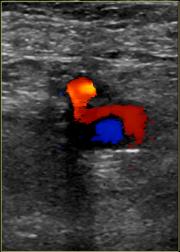

The diagnosis of a pseudoaneurysm is usually made with an ultrasound duplex. There are several signs that a sonographer looks for when insonating with a pseudoaneurysm in mind:

- A mass of blood next to the common femoral artery

- A connection between the mass and the artery (the “stem” of the pseudoaneurysm)

- The power doppler characteristics of blood flow in the stem are to and fro (back and forth). This represents the relationship between the hight pressure artery and the low pressure pseudoaneurysm.